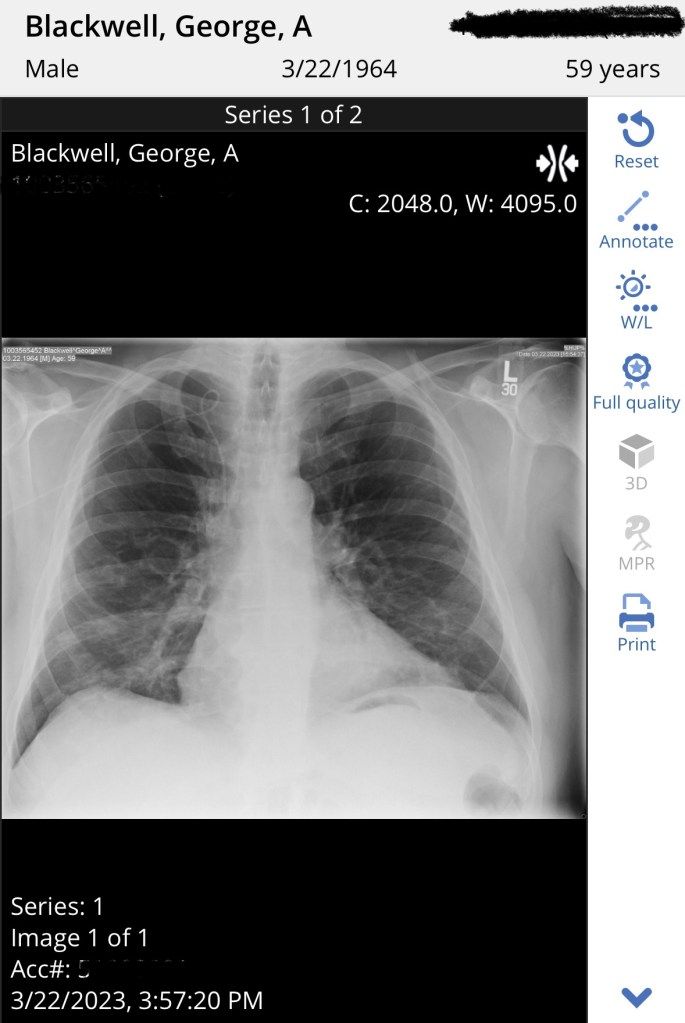

Dr. Loren started by asking George how he was doing and we told her about his fatigue and being extremely winded (or as George put it, “smoked”) after showering or climbing the stairs. She said his hemoglobin is a bit low and that could cause it. Of course, we expected it to be low because he is undergoing chemotherapy. Then he told her about his relentless cough, that sometimes makes George gag and brings him to tears because of the sheer exhaustion of it. He has had this cough since he contracted COVID-19 and subsequently pneumonia in January, but it seemed to be improving for a while. Then it just got worse. She saw that an X-ray had already been ordered by the on-call oncologist to check the placement of his PICC line, due to a concern that arose from George stumbling and catching himself with the arm that has the PICC line. So we would head to radiology after we finished with Dr. Loren. She listened to his lungs and she said they sounded clear. That’s good!

Last stop was radiology where George got his chest X-ray and then we headed to the parking garage and got in the car and headed for home. On the way home, George was looking at the results from his tests, and saw his X-ray results already! His PICC line was fine, but the radiologist said his impression was “patchy airspace opacities in both lung bases concerning for multifocal pneumonia.” Great. A message from a member of the oncology team let George know that they had called in a prescription for the antibiotic Augmentin in to our local pharmacy. We stopped on the way home and picked it up.